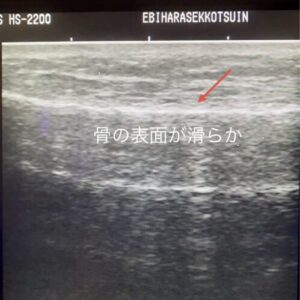

下の画像は、健康な骨の表面を超音波エコーで観察したものです。白く滑らかに写っている線が、正常な骨の表面(骨皮質)です。

疲労骨折の初期段階では、この正常な画像に2つの大きな変化が現れます。

まず、この白い線の上に、骨を覆う**「骨膜」が炎症を起こして黒っぽく厚く写ります。さらに、ドップラーという血流を観察する機能を使うと、その厚くなった骨膜の中に、修復のために集まった新生血管が「赤や青の点(血流信号)」として多数観察されます。**

この「骨膜の肥厚」と「血流の増加」こそが、レントゲンに写る前の、骨が発している重要なSOSサインなのです。